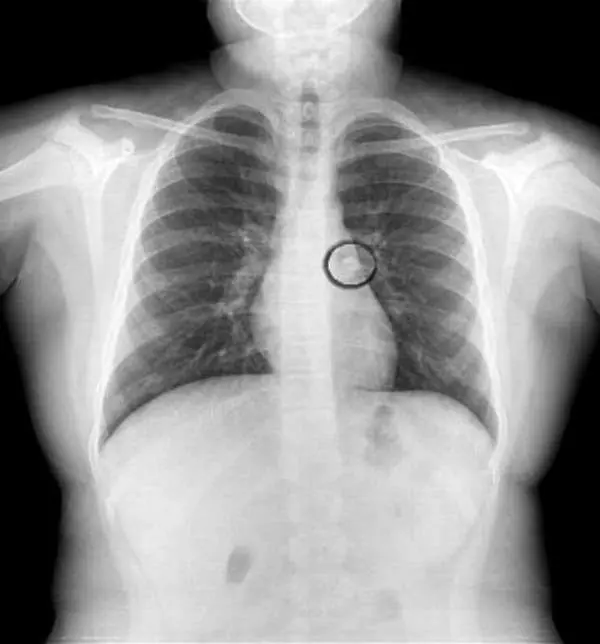

پزشک برای تشخبص دقیق و تبدیل شکش به یقین پیش از بازگو کردن حدسش عکسبرداری را تجویز کرد تا با توجه به نتیجه عکسبرداری علت را دقیق تر تشخیص دهد ؛ نتیجه همانی شد که پزشک حدس میزد و دندان ناپدید شده داخل ریه ی کودک دیده شد.

در واقع دندان لق شب هنگامی که کودک خواب بوده از لثه جدا شده و به وسیله ی کودک بلعیده شده بود و وضعیت او هنگام خواب دندان را به سمت مسیر تنفسی و بخشی از ریه اش کشانده است که این موقعیت خطرناک است و در صورتی که فرد متوجه نشود می تواند موجب مرگ شود چراکه مانع از رسیدن اکسیژن به اندازه کافی و مورد نیاز به ریه ها و بدن می شود.

پزشک معالج این دختر میگوید :در بررسی های عملکرد ریه ها متوجه شدم که ریه ی سمت چپ او به صورت طبیعی کار نمیکند بنابراین فورا بعد از عکسبرداری برای خارج کردن دندان از ریه اقدام شد و با نوعی لوله موفق به این کار شیدم و کودک را از خطر نجات دادیم.